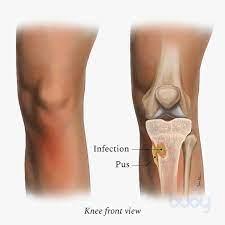

Bone and joint infections include septic arthritis, prosthetic joint infections, osteomyelitis, spinal infections (discitis, vertebral osteomyelitis and epidural abscess) and diabetic foot osteomyelitis. All of these may present through the acute medical take.